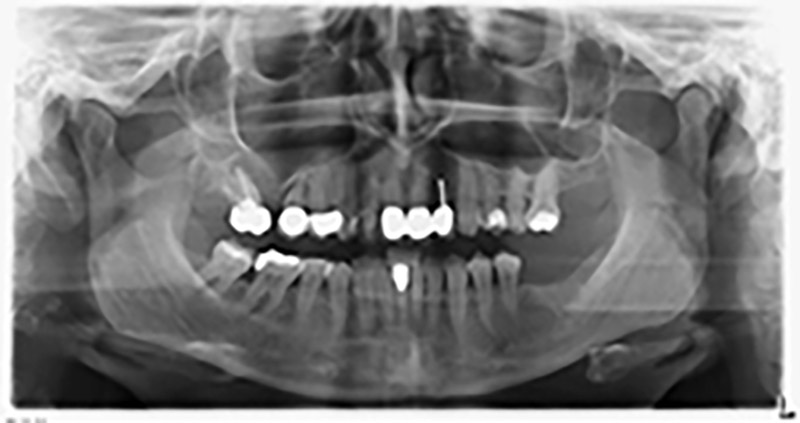

Unos seis meses después de la extracción de las piezas 16 y 14 se realizó una tomografía digital de volúmenes (DVT, Planmeca) para realizar una planificación adecuada y reducir los riesgos al mínimo. En este punto se constató que el hueso no se había regenerado en la cantidad deseada (figuras 2 a 7).